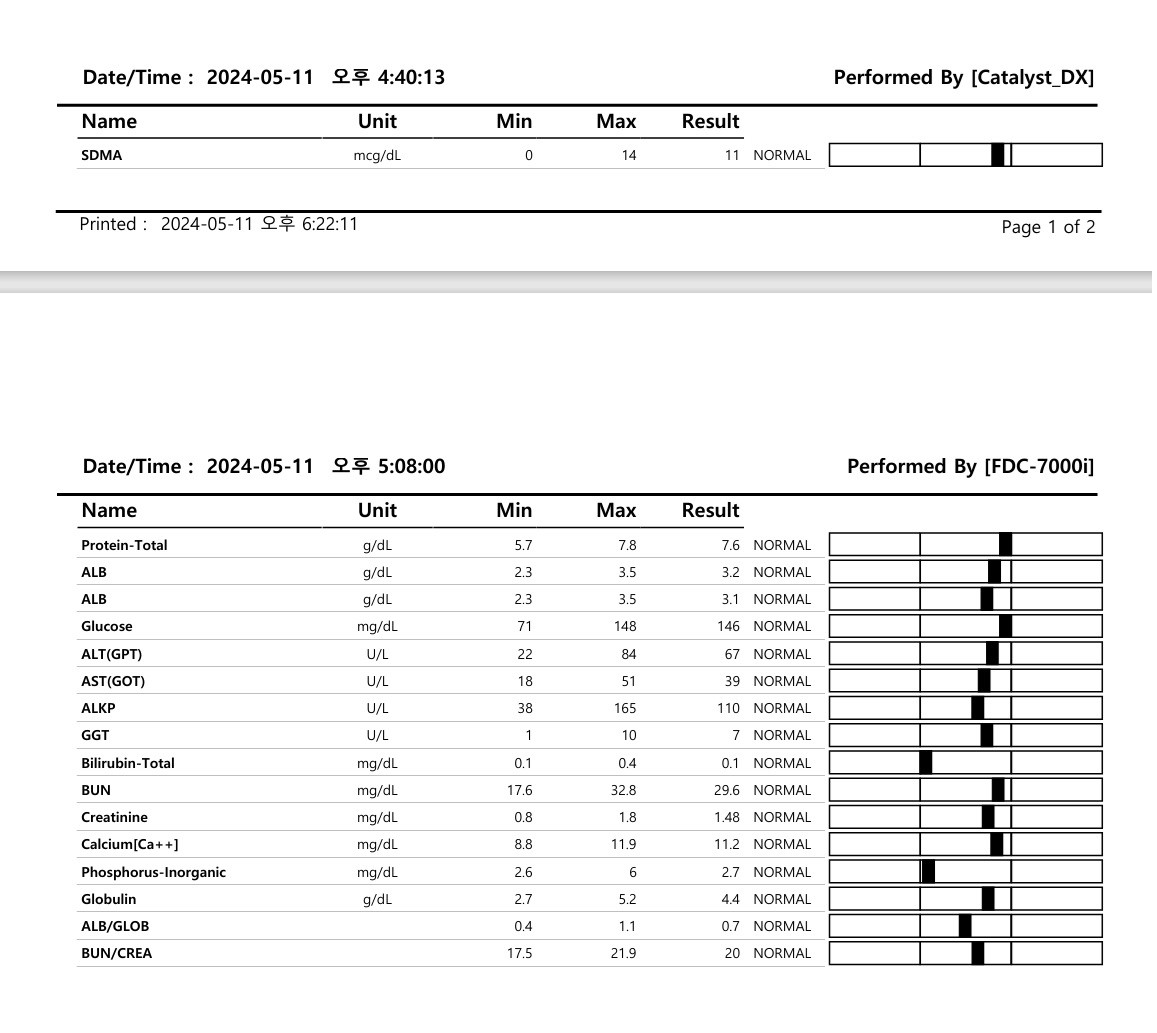

혈액검사, 간기능검사, 신장기능검사,

SDMA신부전조기검사를 했고

정밀복부초음파를 진행했다.

혈액검사결과는 좋다고 하셨다!